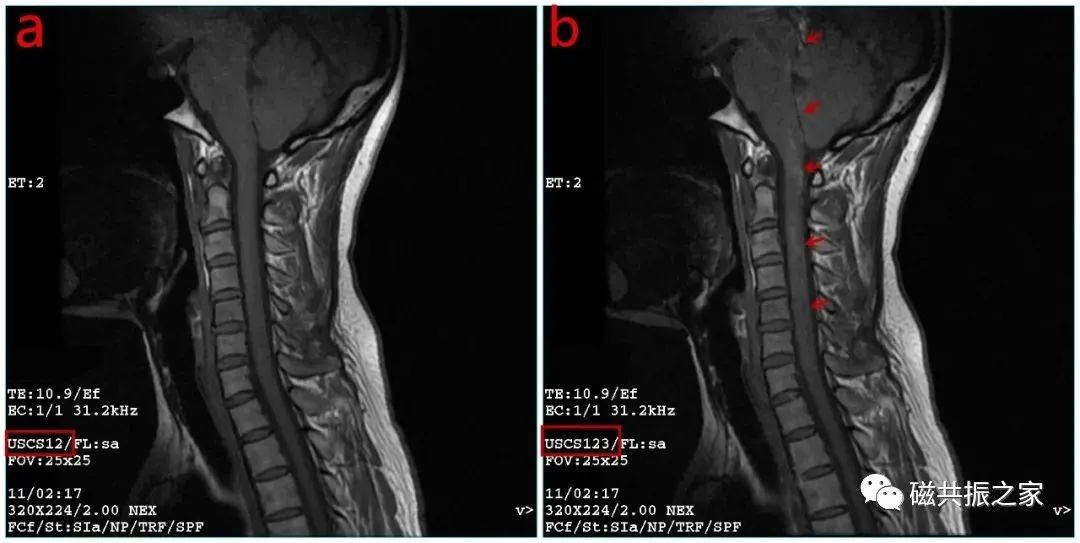

脑脊液流动伪影常易误诊为病变,需与椎管内占位相鉴别。如脊髓背侧脑脊液中可见多个不连续的低信号区,在不同序列成像中表现不同,有时可通过梯度回波 T2 加权像消除此伪影。

运动伪影由心脏和患者运动引起,像颈部吞咽动作引起的伪影可能被误认为脊髓病变,添加颈前饱和带可抑制。